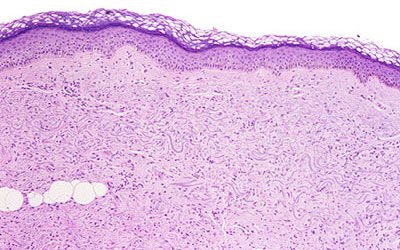

![]() |

| Extensive thickening of the skin, often associated with brawny hyperpigmentation and, in some cases, distinct papules and subcutaneous nodules. Cowper SE. Nephrogenic Fibrosing Dermopathy [NFD/NSF Web site]. 2001-2007. Available at www.icnfdr.org. Accessed 3/5/2007. |

NSF involves a systemic restructuring of tissues. Often, it appears as thickened skin so rigid that makes it difficult to bend the joints. As a result, NSF was originally called nephrogenic fibrosing dermopathy (NFD), but underwent a name change to reflect the systemic nature of the disorder, which can include fibrosis of the skeletal muscle, bone, lungs, pleura, pericardium, myocardium, kidneys, muscle, bone, testes, and dura.